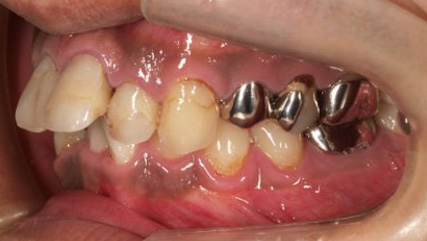

乱ぐい歯、でこぼこがとても酷い状態になります。歯が前後的に重なってしまっている、八重歯になっているなどがこのジャンルに入ります。

顎の大きさと歯の大きさのギャップが大きく、時には歯を抜かないと矯正治療ができない場合もあります。当院では治療期間が長くなるが抜かない治療方針など、一つの治療プランだけでなく、さまざまな可能性の治療方針を説明させて頂くよう心掛けております。こういった考え方はインフォームド・チョイスと言われ近年大切にされている考え方と言われております。

治療前

治療終了前

下顎が上顎より前に出ている状態です。お顔つきも、下顎の先(オトガイ)が前に出ているような横顔になる場合が多いです。前歯が咬んでいないことが多く、奥歯への負担が大きい状態になります。そのままのかみ合わせを続けてしまうと、奥歯がかけたり、割れたりするリスクが高まります。歯列矯正では奥歯の位置をコントロールし、前歯のかみ合わせを作る治療方針を立てます。ごく稀に、歯列矯正ではかみ合わせを作れない場合もあり、その場合は外科矯正という手段を用いて矯正治療をしなければいけません。受け口は、遺伝性が強いとも言われておりますので、そういった情報も考慮し、治療を進めていくことが大切です。